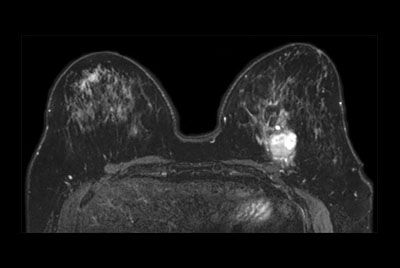

Breast biopsy with dS Sentinelle Breast coil

Dynamic Breast imaging with SmartSpeed AI

Breast 3D and 4D imaging